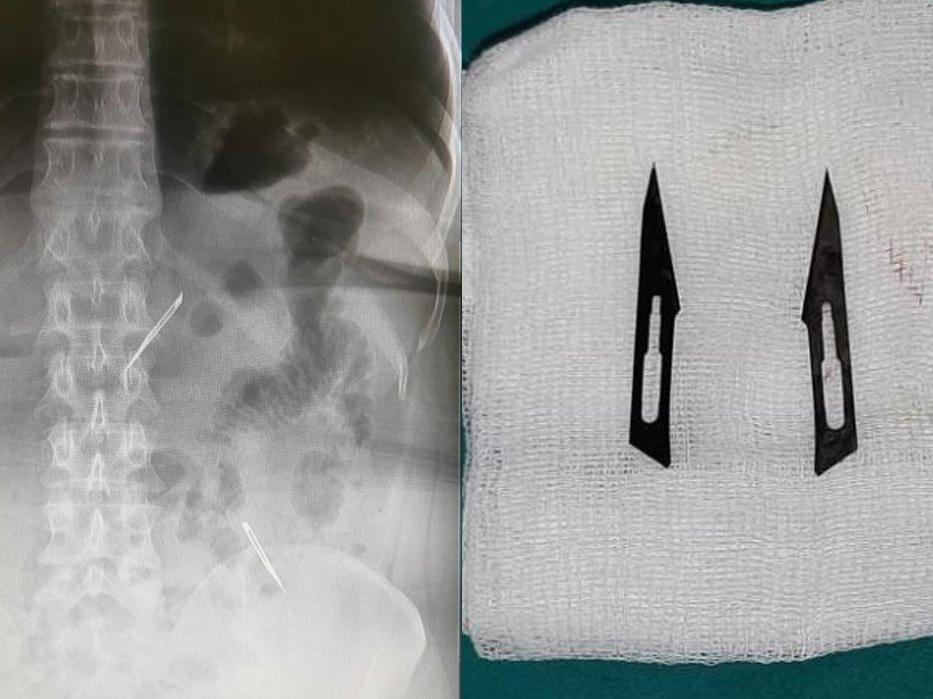

Sağlık Bilimleri Üniversitesi Ankara Atatürk Sanatoryum Eğitim ve Araştırma Hastanesi’ne mide ve karın bölgesinde aşırı ağrı şikayeti ile müracaat eden 46 yaşındaki D.E.’nin yapılan tahlil, tetkik ve çeşitli görüntülemelerden sonra bağırsak kısmında 2 adet neşter olduğu tespit edildi.

Genel cerrahi kliniği tarafından zorlu bir ameliyat sonrasında neşterler kadının vücudundan çıkarıldı. 46 yaşındaki D.E. neşterleri nasıl yuttuğunu bilmediğini tahminen ekmek ile birlikte yutabilmiş olabileceğini ifade etti.

Ameliyatı gerçekleştiren Sağlık Bilimleri Üniversitesi Ankara Atatürk Sanatoryum Eğitim ve Araştırma Hastanesi Genel Cerrahi Kliniği Eğitim ve İdari sorumlusu Prof. Dr. Hakan Buluş ise hastanın yoğun şikayetleri üzerine çektikleri röntgen sonrasında 2 adet neşteri görünce şaşkına uğradıklarını söyledi.

Hastanın şikayetlerinin artması üzerine gerçekleştirilen tetkiklerde 46 yaşındaki kadının karın bölgesinde 2 adet yabancı cisim olduğunu tespit ettiklerini, detaylı inceleme sonucunda bu cisimlerin neşter olduğunu fark ettiklerini belirten Prof. Dr. Buluş,

“Yaklaşık 10 gün önce kliniğimize karın ağrısı ve bulantı şikayetleri ile başvurdu. Bizim yaptığımız fiziki muayene ve tetkiklerinde hastanın direkt karın grafisinde 2 adet yabancı cisim olduğunu tespit ettik.

Sonrasında 2 adet yabancı cismin bistüri (neşter) ile uyumlu olduğunu gördük. Bunun üzerine hastanın şikayetlerinin de artması üzerine, ameliyat kararı verdik. Yaptığımız ameliyatta ince bağırsağın yaklaşık 180’inci santimetresinde bu yabancı cisimlerin olduğunu tespit ettik.

Bunun üzerine ameliyatla bunları çıkarttık. Hastamızın sağlık durumu şuan gayet iyi. Ameliyattan sonraki üçüncü günü. Şuan bir problemi yok, inşallah birkaç gün içerisinde şifa ile taburcu etmeyi düşünüyoruz” şeklinde konuştu.

Çıkardıkları cismin, neşterin normalde ameliyatlarda kullanılan bir malzeme olduğunu söyleyen Prof. Dr. Buluş, “Çıkardığımız yabancı cisimler bizim ameliyatlarda sıkça kullandığımız 11 numara dediğimiz bir bistüri tipi. Ebatları da yaklaşık 4 santime yarım santim ebatlarında.

Ucunun sivri olması nedeniyle ince bağırsak mukozasına saplanarak enflamasyon ve bir karın ağrısı yapması, sonrasında da ağrı şikayetlerinin artmasına neden olmasından dolayı ameliyat kararı verdik” diye konuştu.